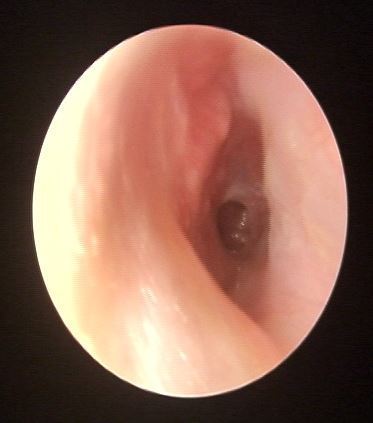

最近遇到一些關(guān)于鼓膜穿孔的爭(zhēng)論,醫(yī)患的角度不同,理解不同,醫(yī)生可以很理性,而患者牽涉自身,往往很感性。非常理解,但是知識(shí)相通才可以構(gòu)建交流的橋梁。所以,關(guān)于鼓膜穿孔這件事兒,想給大家普及一點(diǎn)知識(shí),以便大家可以理性健康的對(duì)待我們的耳朵??耳從解剖角度分外耳、中耳及內(nèi)耳,鼓膜位于外耳道底部,與外耳道有一個(gè)大約45度的夾角,鼓膜的主要作用是聲波傳導(dǎo)作用,由于鼓膜的解剖位置及外耳道與中耳腔微生物環(huán)境的不同,鼓膜也有分界外中耳,起到楚河漢界的作用。最常見的鼓膜穿孔的因素有兩類,一類是耳外傷,另一類是急性炎癥。耳外傷常見的有不良挖耳習(xí)慣損傷,比如掏耳朵不慎棉簽捅入鼓膜導(dǎo)致?lián)p傷,此外,還有打架耳光損傷以及一些重大交通事故損傷。另一類導(dǎo)致鼓膜穿孔的因素多為感染,急性上呼吸道感染后引發(fā)急性中耳炎,耳痛劇烈,流膿,流膿后耳痛減輕。尤其是在兒童期,夜間發(fā)熱、耳痛,急診檢查鼓膜充血紅腫,用藥一兩天發(fā)現(xiàn)耳道內(nèi)多量血性分泌物,大多為急性炎癥刺激導(dǎo)致鼓膜穿孔,檢查可以見到鼓膜表面有光點(diǎn)波動(dòng)—俗稱燈塔征,是中耳膿性分泌外涌的表現(xiàn)。亦有部分反復(fù)發(fā)作的慢性外耳道炎患者,多有不良掏耳習(xí)慣,反復(fù)挖耳或者清理沖洗,炎癥初始分布外耳道,后進(jìn)一步波及鼓膜,導(dǎo)致鼓膜表面有炎癥滲出及肉芽生長(zhǎng),鼓膜菲薄,外力作用或炎癥進(jìn)一步刺激,可導(dǎo)致鼓膜穿孔。鼓膜的生理作用為傳音、分界外中耳的作用,當(dāng)發(fā)生鼓膜穿孔后,鼓膜的傳音作用受到影響,故而多數(shù)穿孔患者都有一定程度的聽力損失。國(guó)內(nèi)外學(xué)者的研究顯示:穿孔越大,聽力損失越重。大部分鼓膜穿孔都有25-40分貝左右的聽力損失,當(dāng)然,鼓膜穿孔導(dǎo)致的聽力下降,也與中耳容積及中耳粘膜的狀態(tài)有關(guān)系。此外,由于外中耳的楚河漢界被破壞,外耳道與中耳腔相通,外源性的感染因素可以直接進(jìn)入中耳,導(dǎo)致中耳炎的發(fā)生。同時(shí),中耳腔被覆粘膜組織,而外耳道是上皮為主,兩者在酸堿度及濕度上均有不同,外中耳交通,易導(dǎo)致外耳道炎癥的發(fā)生。外傷因素導(dǎo)致的鼓膜穿孔,多為裂隙狀、不規(guī)則形穿孔,治療上要求患者保持外耳干燥、禁用滴耳液,適當(dāng)抗炎預(yù)防感染,大多數(shù)外傷性鼓膜穿孔多在兩周到一個(gè)月左右愈合,如果超過三個(gè)月沒有愈合,考慮外傷性鼓膜穿孔無法自愈,就需要進(jìn)一步手術(shù)干預(yù)。穿孔的愈合過程為鼓膜表面上皮向?qū)?cè)爬行的過程,最終會(huì)使不規(guī)則形狀的穿孔愈合。上皮爬行過程可使鼓膜穿孔相鄰邊緣愈合,上皮進(jìn)一步向內(nèi)側(cè)爬行,由不規(guī)則的穿孔,變?yōu)閳A形、橢圓形、腎形或者馬蹄形。故而,慢性反復(fù)發(fā)作的中耳炎,多難自愈,其穿孔也多為近圓形、橢圓形或腎形的。穿孔的病理狀態(tài)存在,使中耳腔不定期處于感染狀態(tài),或有反復(fù)流膿的,也有炎癥過度反應(yīng),使鼓室內(nèi)粘膜玻璃樣變性,進(jìn)而進(jìn)一步導(dǎo)致聽力下降,這就是中耳炎最常見的并發(fā)癥--鼓室硬化。故而,對(duì)于鼓膜穿孔的患者,建議患者選擇合適的時(shí)機(jī),行手術(shù)修補(bǔ)。

兒童鼓膜穿孔,原來微創(chuàng)手術(shù)就可以解決,再也不用等了

中耳炎鼓膜穿孔,原來微創(chuàng)手術(shù)這么簡(jiǎn)答